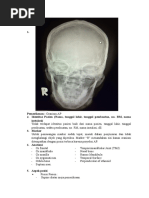

Pemeriksaan Maag Duodenum (Proyeksi PA post kontras)

Radiographic Critique Form (RCF)

Examination = Pemeriksaan Ya Diskripsikan hasil analisis

Maag Duodenum Atau

Proyeksi PA post kontras Tidak

Persyaratan identifikasi Tidak Dalam radiograf tidak terdapat ID

pasien, yang meliputi nama

pasien, no. RM, tgl pemeriksaan,

nama instalasi.

Penempatan marker dengan Tidak Karena dalam radiograf tersebut

benar tidak terdapat marker

Gambaran anatomi dalam Gambar yang seharusnya tampak

radiograf? pada radiograf meliputi Lambung

yang terisi barium.

Apakah gambaran anatomi Ya Radiograf telah sesuai dengan

tampak sesuai dengan proyeksi proyeksi. Proyeksi yang

ini? digunakan yaitu proyeksi PA

Apakah kolimasi lapangan Ya Luas lapangan cukup

radiasi cukup? Dan tetap menampakkan objek sehingga

mengindahkan ALARA tidak ada objek yang terpotong

(limitasi, justifikasi, optimasi)? dan pengulangan foto.

Proteksi radiasi, presentasi, Tidak Penggunaan kolimasi yang sesuai

menghalangi gambaran obyek? sehingga tidak ada objek yang

terpotong dan pengulangan foto.

Garis tepi luar kortek tulang, Ya Garis tepi tulang terlihat jelas.

patren trabekula tulang, dan atau Trabekula tulang terlihat jelas.

struktur soft tissue terlihat Struktur soft tissue terlihat samar

tajam?

Radiograf terlihat tanpa distorsi? Ya Tidak terdapat magnifikasi dan

6

distorsi yang dapat mengganggu

diagnosa. Ditunjukkan dengan

anatomi radiografi yang

ditunjukkan dalam ukuran

anatomi yang normal.

Ukuran film benar, regio organ Ya Ukuran film benar menggunakan

anatomi terlihat sesuai dan ukuran 30x40cm.

benar?

Menggunakan alat penerima Ya Pemeriksaan ini menggunakan

gambar yang sesuai? image reseptor yang sesuai

Kecukupan daya penetrasi sinar Ya Daya penetrasinya baik

dengan kerapatan? ditunjukkan dengan terlihatnya

trabecular tulang dan cortex tulang

terlihat. Densitas sudah cukup

ditandai dengan tampak gambaran

opaq pada daerah tulang dan

gambaran lebih opaq pada

lambung yang terisi MK

Kecukupan kontras gambar? Ya Kontras sudah baik, sudah dapat

menampakkan outline soft tissue

dan outline bone trabecular

Upaya pencegahan terhadap Ya Mengecek dan memantau pasien

artefak gambar? terhadap semua aksesoris yang

mengganggu gambaran radiograf

seperti baju, kalung dan lain-lain

yang berbentuk logam sebelum

dilakukan eksposi

Berapakahkonsentrasidan Dosis yang diberikan sekitar 30-

volume media kontras yang di 120ml dan diencerkan dengan air

butuhkan ? 80ml.

Outcome yang dikehendaki Ya Hasil radiograf sesuai dengan

(contoh; pemakaian sinar-x yang dikehendaki karena dapat

dapat memperlihatkan nilai menampilkan informasi yang

diagnostik dari regio organ ingin ditampilkan.

anatomi)?

Kesimpulan Radiograf ini

adalah :

DITERIMA/ACCEPTED Dengan catatan pada radiograf

DITERIMA harus tercantum identitas pasien

untuk memudahkan penanganan

agar tidak miss diagnosa dan

menghindari pengulangan foto.